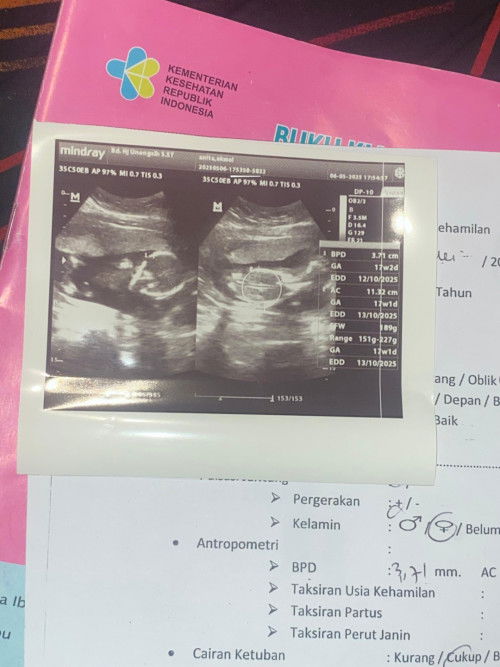

Hpl Oktober lagi musim jk apa nih bund, tadi aku USG 16week katanya perkiraan cewe😁😍